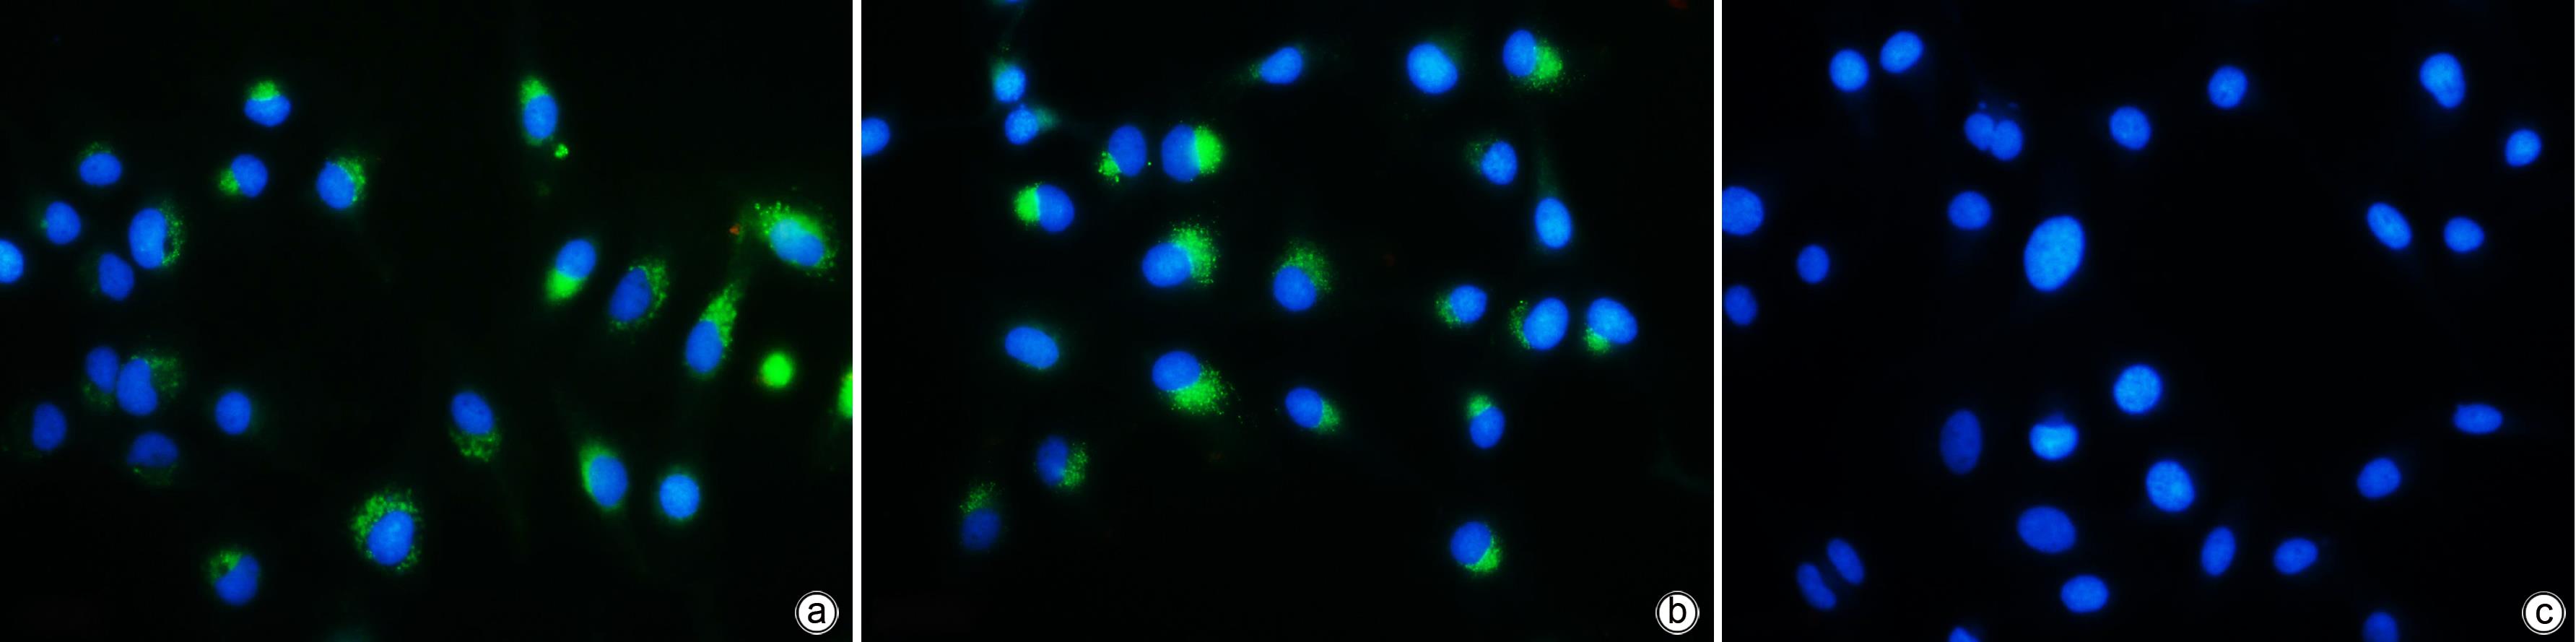

Mechanism of cytotoxic T lymphocyte-derived exosomes inhibiting hepatic stellate cell activation

Chuanfu QIN, Yali ZHAO, Lijuan LONG, Hua QIU

2023, 39(10): 2340-2347. DOI: 10.3969/j.issn.1001-5256.2023.10.011

Abstract(865) HTML (352) PDF (1118KB)(62)

Abstract:

Objective  To investigate whether cytotoxic T lymphocyte (CTL)-derived exosomes can downregulate HBx expression and inhibit hepatic stellate cell (HSC) activation.  Methods  The supernatants of HepG2, HepGA14, and CTL cells were collected to extract exosomes, which were referred to as NC-exo, HBV-exo, and CTL-exo, respectively). Transmission electron microscopy was used to observe their morphology, and Western Blot was used to measure the expression of the markers of exosomes CD63 and TSG101. NC-exo, HBV-exo, and CTL-exo labeled by BODIPY dye were mixed with HBV-exo at different ratios and were then co-cultured with HSC LX-2 (HSC-LX2). A fluorescence microscope was used to observe whether exosomes could enter LX-2 cells, and an fluorescence microscope was used to observe cell morphological changes; quantitative real-time PCR (qPCR) was used to measure the expression of the activated biomarkers such as transforming growth factor-β1 (TGF-β1), ɑ-smooth muscle actin (ɑ-SMA), and collagen type I (Collagen I) in LX-2 cells. CTL-exo was added to the HepGA14 culture system; then qPCR was used to measure the mRNA expression level of HBV DNA, cccDNA, and HBx in exosomes in HepGA14 cells, and Western Blot was used to measure the protein expression level of HBx in exosomes. The t-test was used for comparison of normally distributed continuous data between two groups; a one-way analysis of variance was used for comparison between multiple groups, and the least significant difference t-test was used for further comparison between two groups.  Results  The exosomes were all microcysts with a double-layer membrane structure and were circular or elliptical in shape, with the expression of the signature proteins CD63 and TSG101, and the vesicles had a diameter of 50-100 nm. The fluorescence microscope showed that exosomes could enter LX-2 cells, and HSC were enlarged with extended cell processes. The results of qPCR showed that there were significant differences in the expression levels of TGF-β1, ɑ-SMA, and Collagen I genes between the NC-exo, HBV-exo, NC-exo+HBV-exo, and Con groups (F=444.678, 417.144, and 571.508, all P<0.05). After the intervention of HepGA14 cells with CTL-exo, qPCR results showed that compared with the control group, there were significant reductions in the expression levels of HBV DNA and cccDNA in HepGA14 cells (all P<0.05), the relative mRNA expression level of HBx in exosomes (P<0.05), and the protein expression level of HBx (P<0.05). CTL-exo and HBV-exo were mixed at different ratios (2∶1, 5∶1, 10∶1) and were then used for the intervention of LX-2 cells, and qPCR results showed that the expression levels of TGF-β1, ɑ-SMA, and Collagen I genes in LX-2 cells gradually decreased with the increase in the ratio of CTL-exo between groups (P<0.05).  Conclusion  CTL-exo can downregulate the protein expression of HBx in HBV-exo to inhibit HSC activation, suggesting that CTL-exo has an anti-hepatitis B liver fibrosis effect.